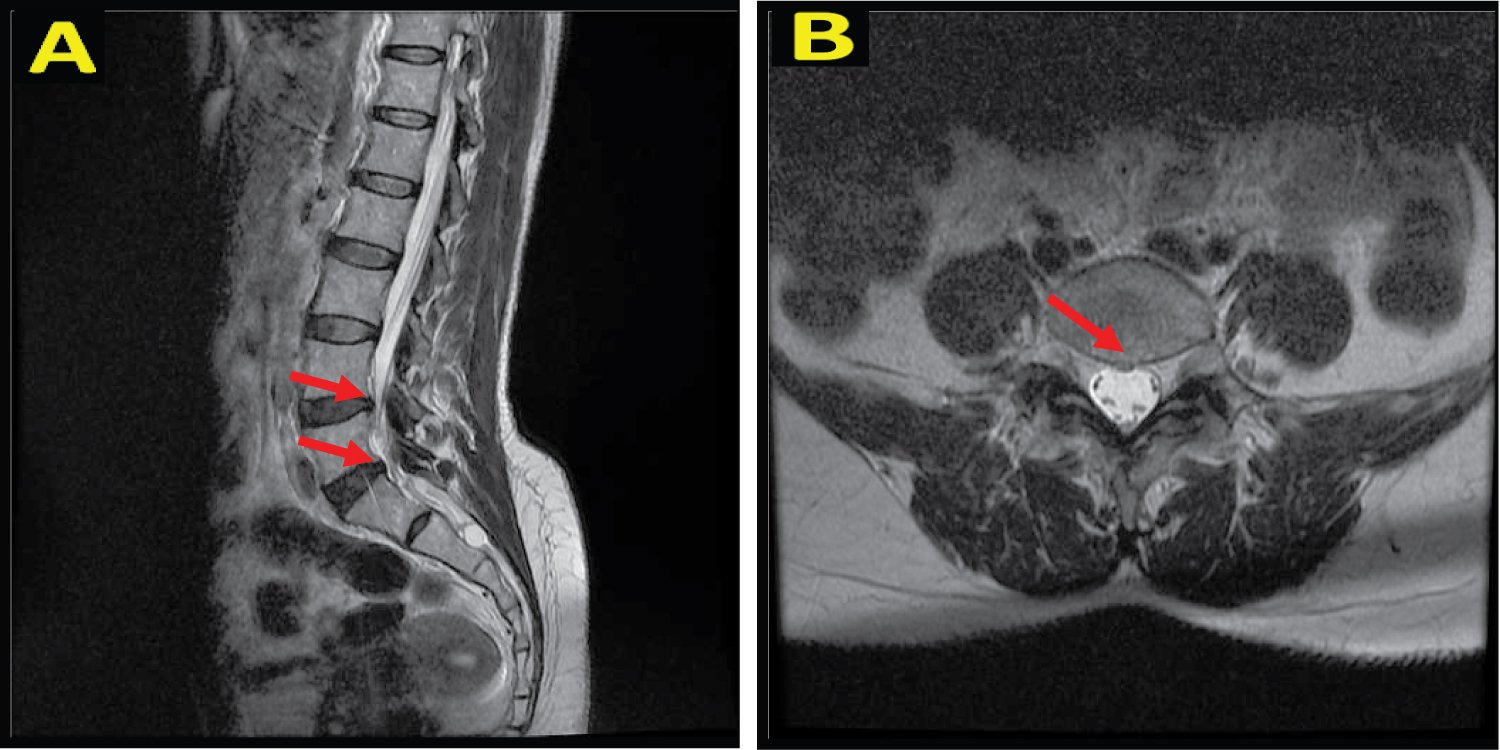

A 48-year-old woman came to the hospital with complaints of lower back pain since 2 months ago. The pain was felt radiates to the lower limbs accompanied by a stabbing feeling, the pain was felt intermittently, the pain worsens at night especially when sitting and sleeping in a soft place, and the pain was reduced when the patient stands up. The patient had a previous history of PSLD surgery at another hospital 3 months ago due to HNP (Figure 1). 6 days after surgery, the patient felt headache, nausea, vomiting, and fainting. Normal bowel and bladder, no history of trauma. On physical examination, there were no lumps in the lumbar spine, motoric and sensory was normal.

Figure 1: A) Sagittal T2 MRI image shows protrusion of the intervertebral disc at L4-L5 and L5-S1 levels; B) Axial T2 MRI image shows protrusion of the intervertebral disc at L5-S1 level towards the posterior central. View Figure 1